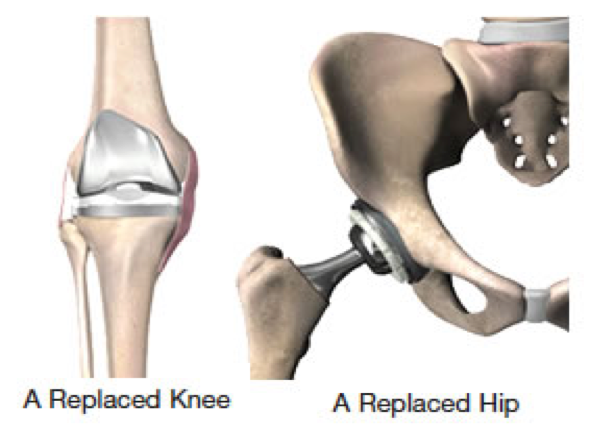

Phẫu thuật thay khớp

16/11/2018

Bài viết cung cấp các kiến thức cần thiết về phẫu thuật thay khớp